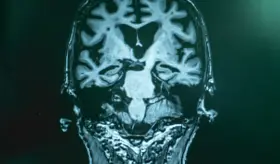

La adherencia al tratamiento es clave para evitar daños cerebrales y facilitar la recuperación en la condición.

Los fármacos para la ansiedad actúan modulando los niveles de neurotransmisores clave en el cerebro, lo que ayuda a restaurar el equilibrio neuroquímico necesario para regular el estado de ánimo y reducir la ansiedad.